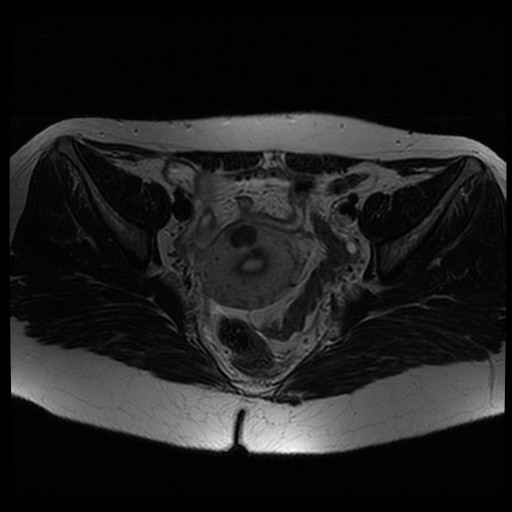

bekken